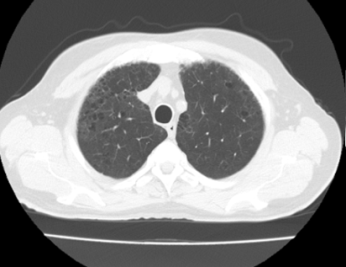

Paciente quien se evalúa en área de consulta, y se solicita tomografía computarizada (TC) de cuello y tórax (Figura 1 y 2), donde se observa obliteración parcial del lumen laríngeo, sin erosión de sus cartílagos, además ganglios linfáticos cervicales bilaterales menores de 1 cm, y a nivel torácico enfermedad bulosa extensa a predominio de lóbulos superiores, sin lesiones nodulares sugestivas de extensión secundaria. Se decide realizar laringoscopia directa más toma de biopsia, en área quirúrgica, donde se evidencia como hallazgos, una tumoración exofítica, friable, que ocupa la cuerda vocal izquierda con infiltración a ambos repliegues aritenoepiglóticos.